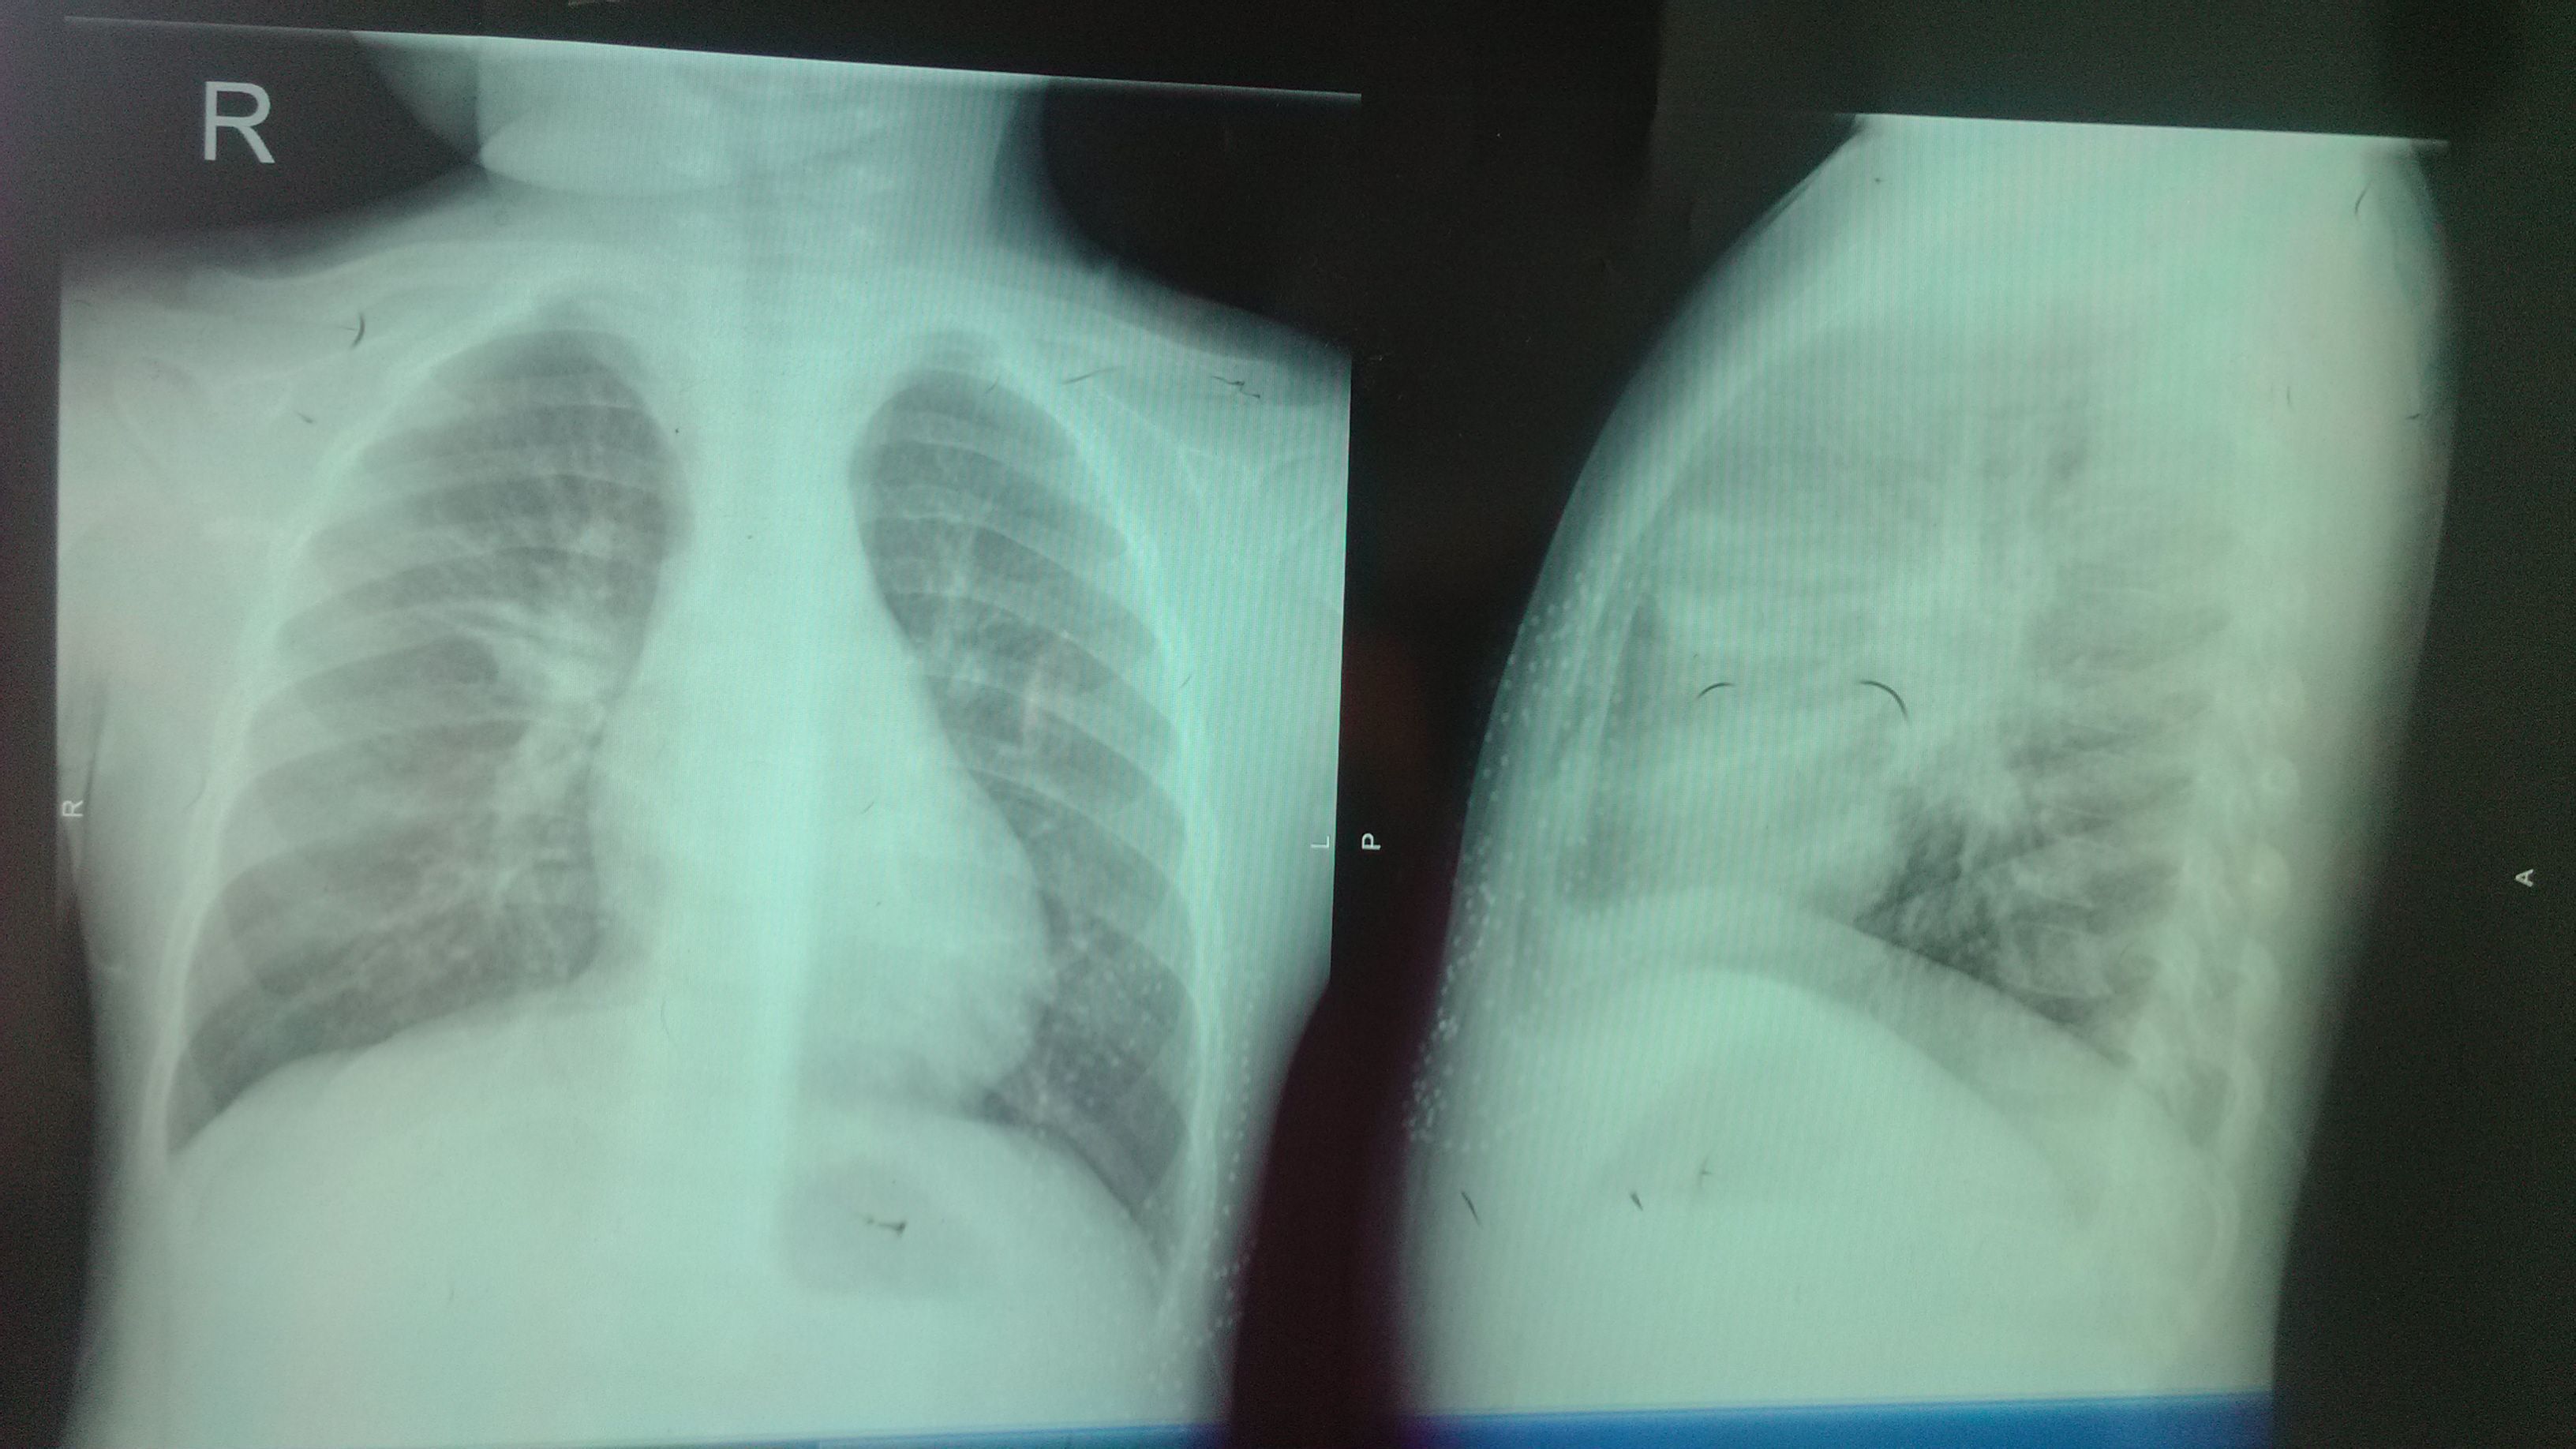

7月2日7月7月您好,我的宝宝四岁,10日前突然咳嗽,7月2日大夫让拍片,结果“阳性。”双肺纹理增多,紊乱,右肺门旁可见片状阴影双肺门影增浓,心影正常,双侧肋膈角锐利,考虑肺门结核可能性大。还验了血常规,白细胞11.81(参考值为4`10),去了结核医院,大夫让先消炎。一个星期之后再拍片。重新看看。是否为结核。开始打针(头孢,炎琥宁,氨嗅索(2)/细心脑(4天)7月7日由于宝宝太胖无法再下针,医生让再次拍片看看,结果“阳性”显示双肺纹理增多,增粗。紊乱,肺野未见活性病变,心影正常,双侧肋膈角锐利。目前宝宝也咳嗽,只是一段时间内会咳嗽。一 天之内咳嗽五次左右。每次咳嗽几下。感觉上像是有痰。睡觉时不咳嗽,不发烧。其它时间没有问题。今年 3月份上幼儿园 ,上火一边打针,一边上学,结果得了肺炎。先后打了23天针。才康复。复查的血常规,白红胞为9.29属参考值内。但血小板,淋巴细胞比率,淋巴细胞数。均偏高。是什么原因呢。还验了微量元素。锌偏低。